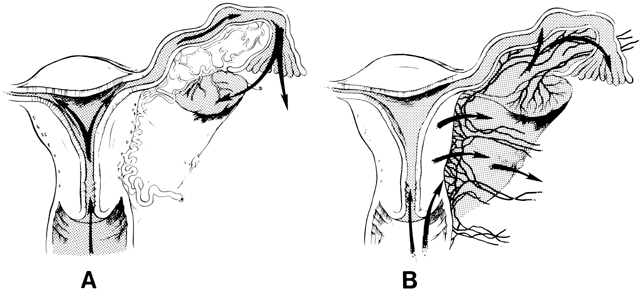

The pathways of spread of genital tract infections are shown in Figure 2. In gonococcal and chlamydial salpingitis, the microorganisms ascend by surface extension from the lower genital tract through the cervical canal by way of the endometrium to the fallopian tubes (Fig. 2A). Microscopically, the endosalpinx is inflamed and edematous. There can be adhesion of the mucosal folds, destruction of cilia, occlusion of the infundibulum, and production of a pyosalpinx. The gonococcal infection may spread beyond the endosalpinx, with possible focal abscess formation and perisalpingitis. In some cases of nongonococcal salpingitis, particularly with M. hominis,73 the pathogens may enter through lesions in the cervix or endometrium and spread to the parametria and tubes through lymphatics and blood vessels (Fig. 2B). The inflammatory swelling that affects the parametria and the tubes is more pronounced than in gonococcal salpingitis, but the endosalpinx is usually intact.

Fig. 2. Schematic drawings of pathways by which genital tract infections spread. A. Direct spread by extension along luminal surfaces is characteristic of gonococcal and chlamydial infection. B. Nongonococcal bacterial and genital mycoplasma infections probably spread to the parametria and fallopian tubes primarily through lymphatics and blood vessels.